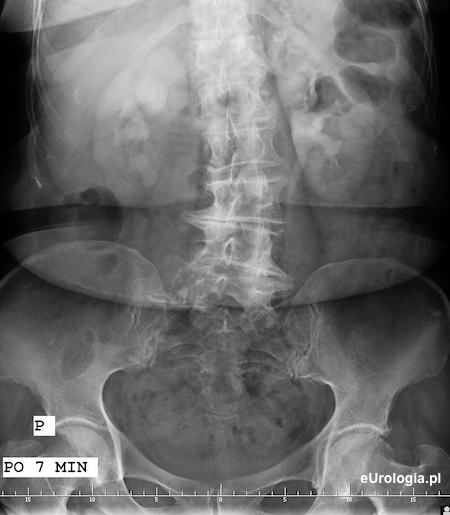

Zdjęcie urograficzne po 7 minutach - uwidoczniono zakontrastowany UKM nerki lewej i górny odcinek lewego moczowodu. Nefrogram i częściowo zakontrastowany UKM prawej nerki.